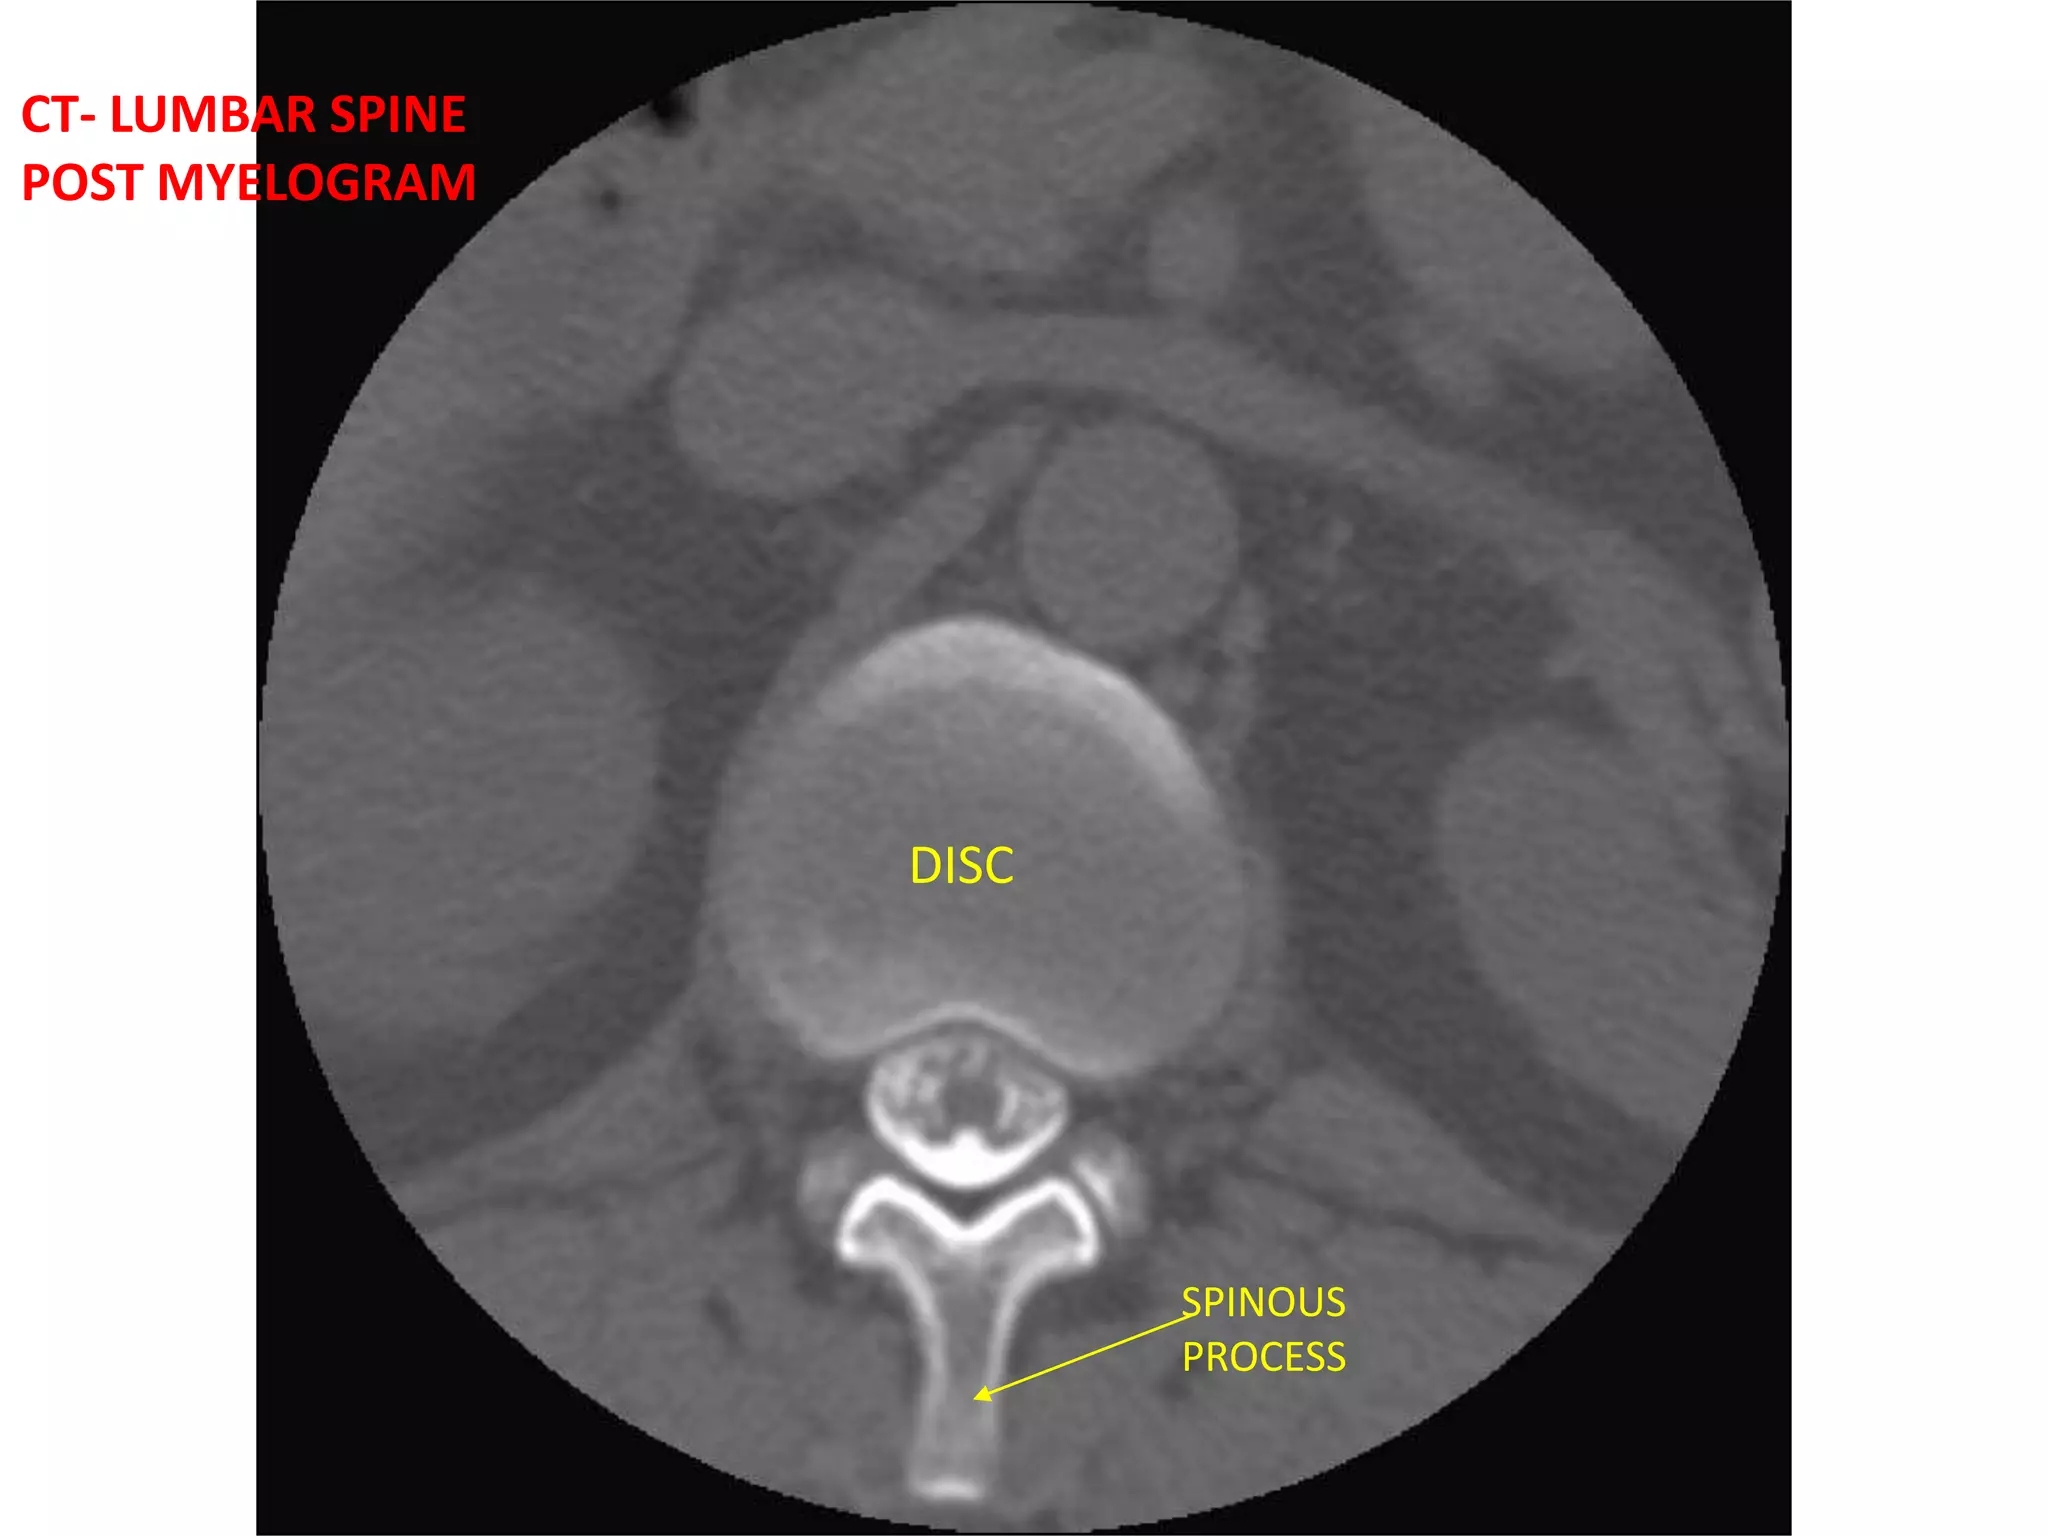

CT- LUMBAR SPINEPOST MYELOGRAM DISCSPINOUS PROCESS

CT- LUMBAR SPINEPOSTMYELOGRAM DISCSPINOUS PROCESS